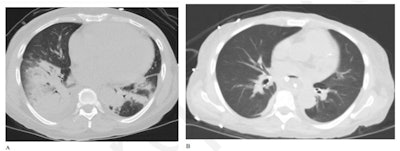

Of the eight individuals, 63% were immunosuppressed when they were admitted, and 75% reported respiratory symptoms. Most (57%) had normal chest x-ray exams. On chest x-ray, common findings were hazy opacities and consolidation, while on chest CT, common findings were ground-glass opacities with mild to moderate severity scores. Two of the eight patients required admission to the intensive care unit. At the end of the study period, 75% were discharged (average length of stay: 13 days).